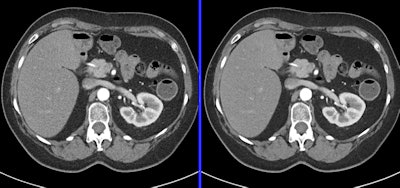

0.2-mSV cardiac CT angiography examination demonstrates standard reconstruction versus iterative model reconstruction (IMR). Image courtesy of Philips Healthcare.

0.2-mSV cardiac CT angiography examination demonstrates standard reconstruction versus iterative model reconstruction (IMR). Image courtesy of Philips Healthcare.Dose-reduction strategies